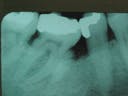

When Mr. Davis first came to our office in 1987, he had a 6 mm pocket on the mesial of tooth #30. Radiographs showed evidence of caries on the distal of the tooth. The patient was subsequently referred to a periodontist for evaluation.

1987